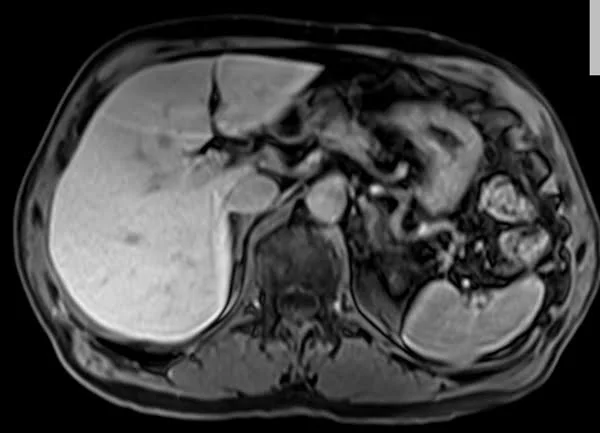

VIBE FAT SAT AXIAL POST CONTRAST SEQUENCE USED IN RENAL IMAGING